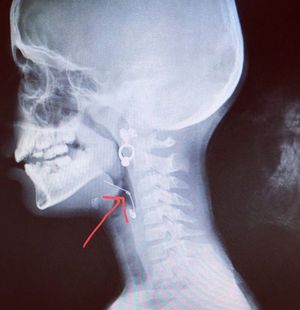

Foriegn body in airway

Open safety pin

Foreign body is in Oesophagus not airway 🤔

True but the tip is still lodged around the pharynx /pharyngeal area, so its partly in the upper airway.

Will it be in pyriform fossa?